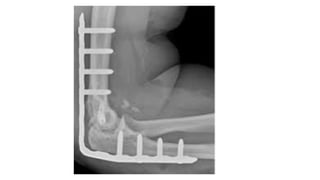

BRIDGE PLATE

• In pa)ents with residual instability that are not candidates for an

external fixator, a temporary bridge plate may be employed.

• IndicaGons

• Condi)ons where maintenance of reduc)on is challenging such as

morbid obesity and pa)ents with neurologic injuries such as

spas)city or flaccid paralysis.

• AJer repair of the collateral ligaments narrow 4.5-mm large

fragment locking plate is bent to 90 degrees.

• A triceps-spliUng approach is employed proximally to iden)fy and

protect the radial nerve.

• The triceps can be leJ aQached to the olecranon.

• Three to four locking screws are placed in the ulna and the distal

humerus avoiding the ar)cula)on and fossae.

• The plate is removed at 4 weeks, and a posterior capsulectomy and

an elbow manipula)on can be considered at the )me of plate

removal to increase the recovery of mo)on.